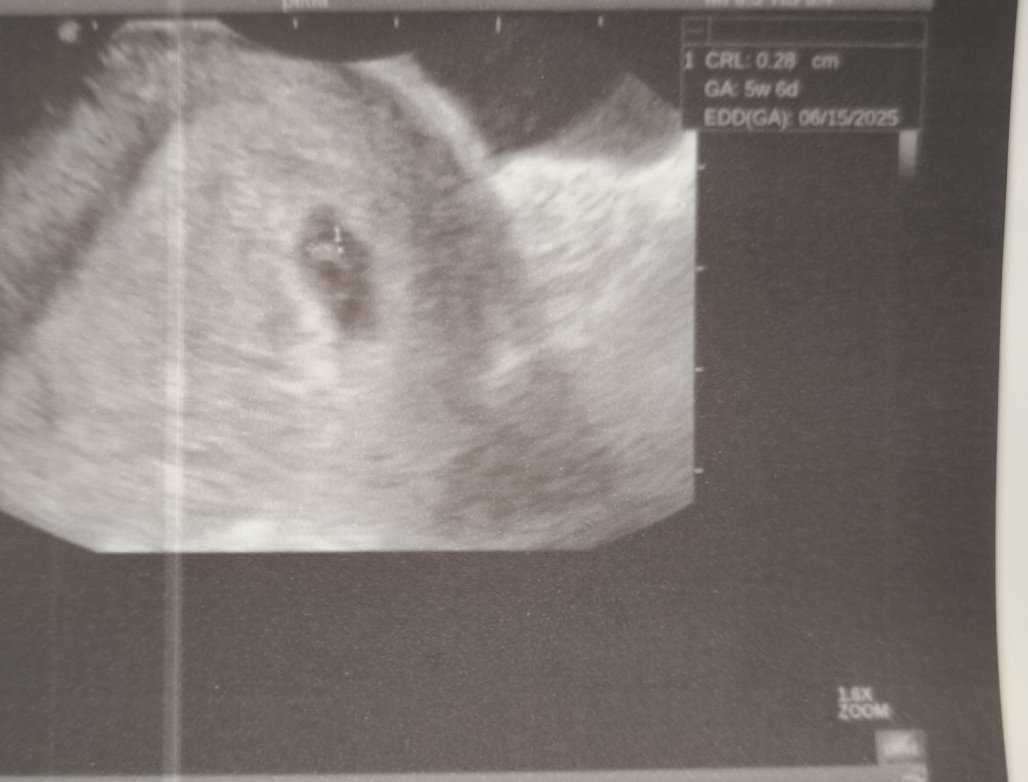

Оказа се, че има отлепване и то доста голямо, около 2 см. Ембрионът е жив, има сърдечна дейност. Изписаха ми утрогестан 2*2 , но шпа 3*2, вит. Ц , спирам аспирина и го заменям с вит. К.  и да пазя леглото.

На последния преглед беше 9.8 см във вторник, но сега не ми каза и не го е записал. Само каза, че е по-голям от отлепването. Аз бях прекалено разревана, за да се сетя да питам (яко ме е ударил хормона, по принцип не съм ревлива 😃) Прикачвам двете снимки от ехографа. Май е записал, че ембриона е 0. 28 см